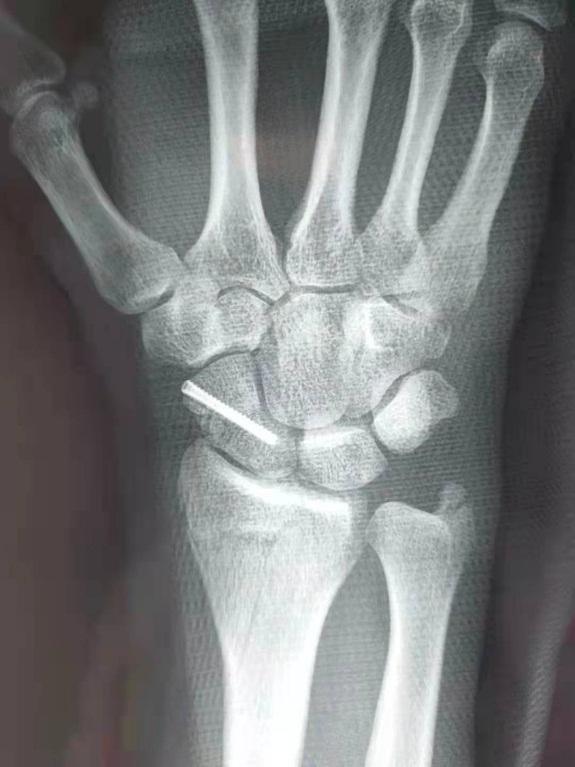

骨伤科主任于海国为约克做了全面的查体,诊断为右腕部骨折,需要手术治疗。然而在与患者交流手术问题的时候却遇到了困难,约克来到中国工作已有20多年,汉语水平也相当不错,但是专业的医学术语他还是无法正确理解。为此,科室医护人员通过翻译软件,还把平时不常用的英语字典都拿了出来,在短时间内终于向约克表述清楚了治疗方案。约克一边给医生竖起了大拇指,还用汉语跟大家说:“我相信你们,我选择手术!”接诊次日,于海国主任带领团队为约克进行了手术,术后恢复良好。